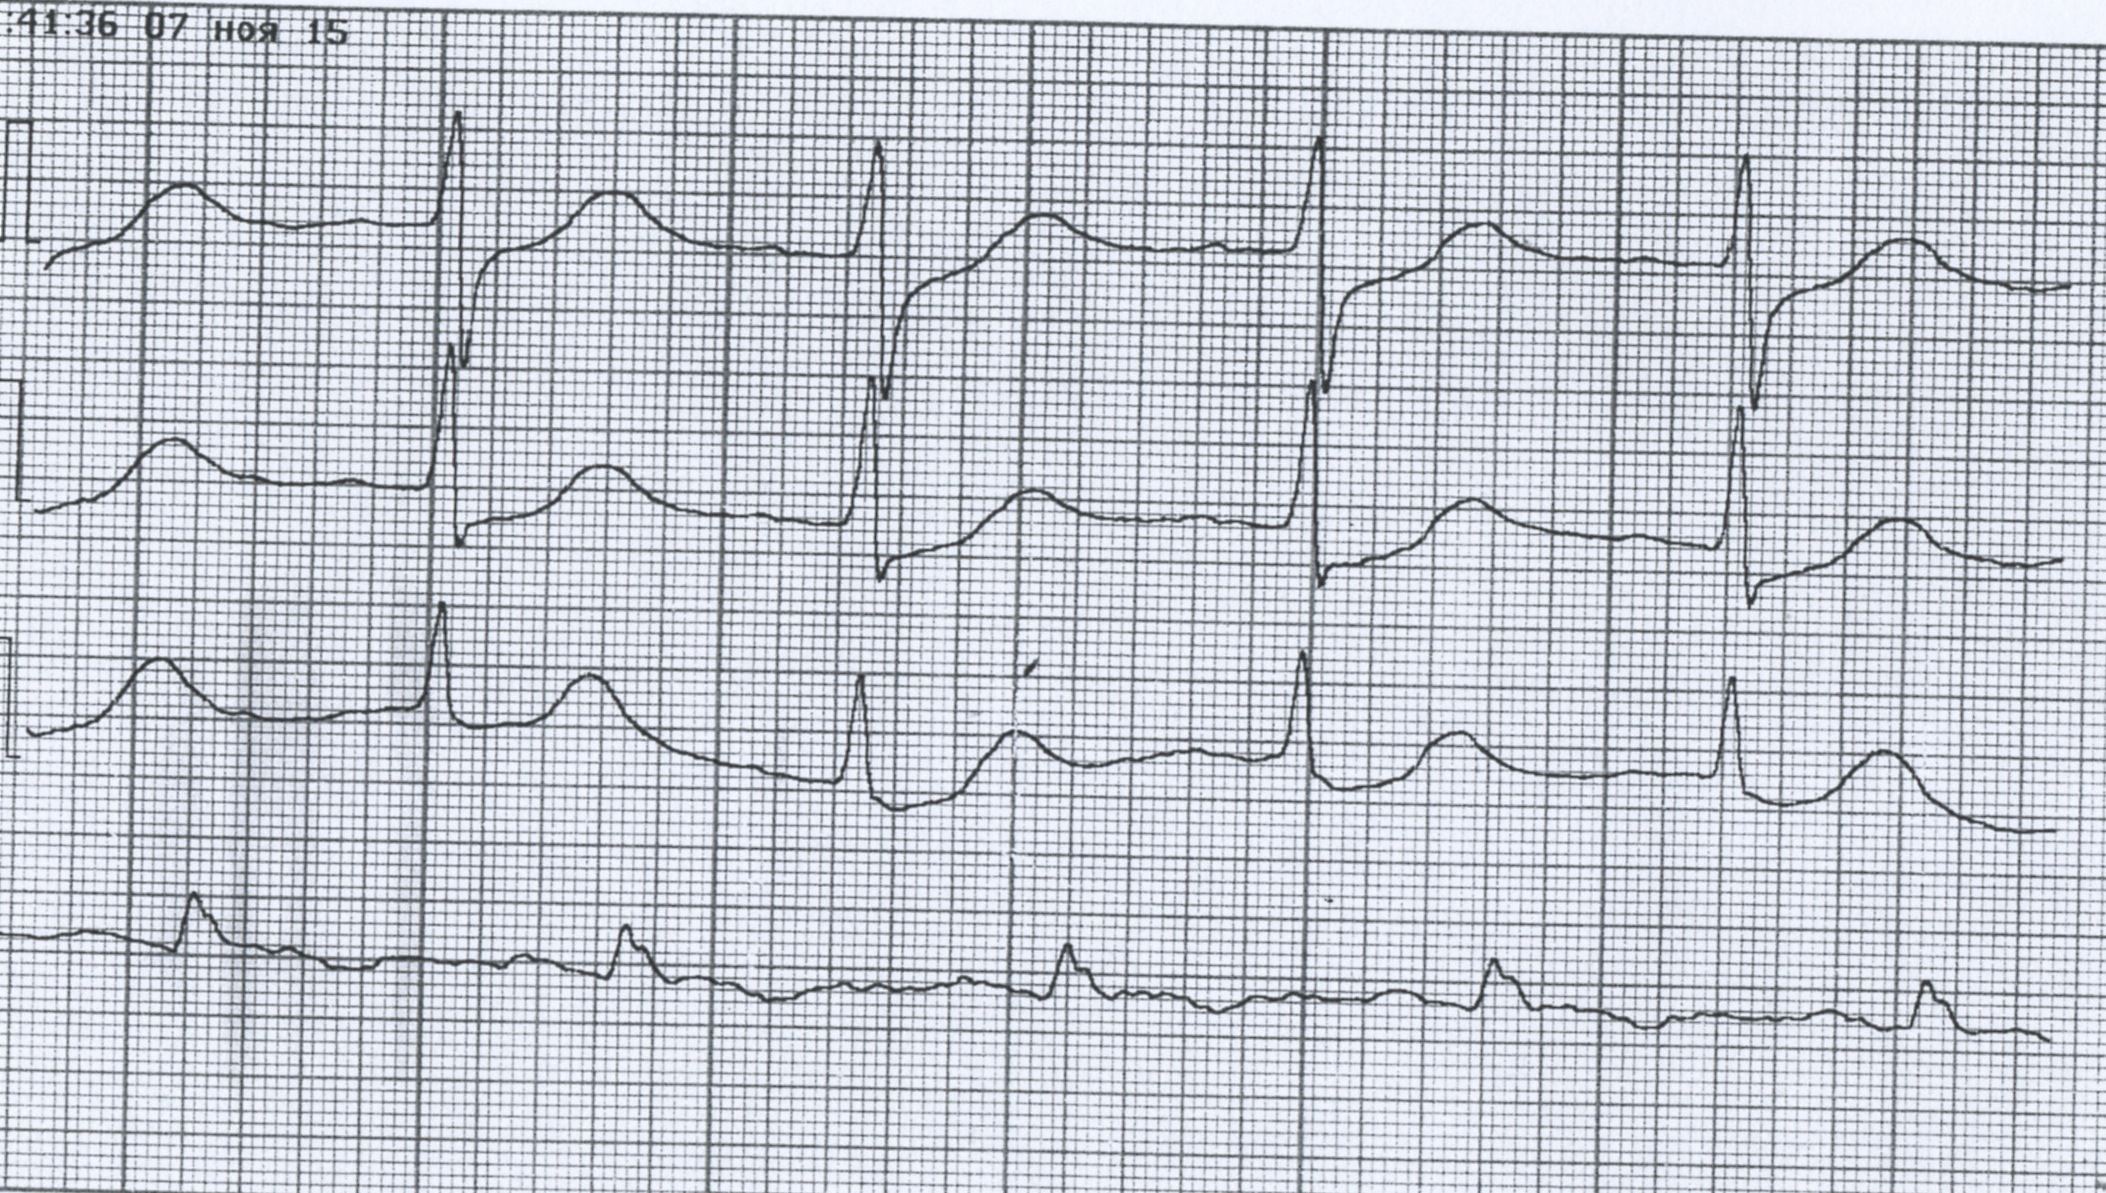

Второй F аккурат проецируется в центр QRS

ЧПС 240 в мин - (второй F) - см. восходящее колено R V2

Медленное ТП. Две ЭКГ одного пациента.

ТП 2:1.

ТП

Медленное ТП

ТП 4:1. Хорошо видно в v1

ТП, а не пейсмекерная тахикардия

ТП 1:1